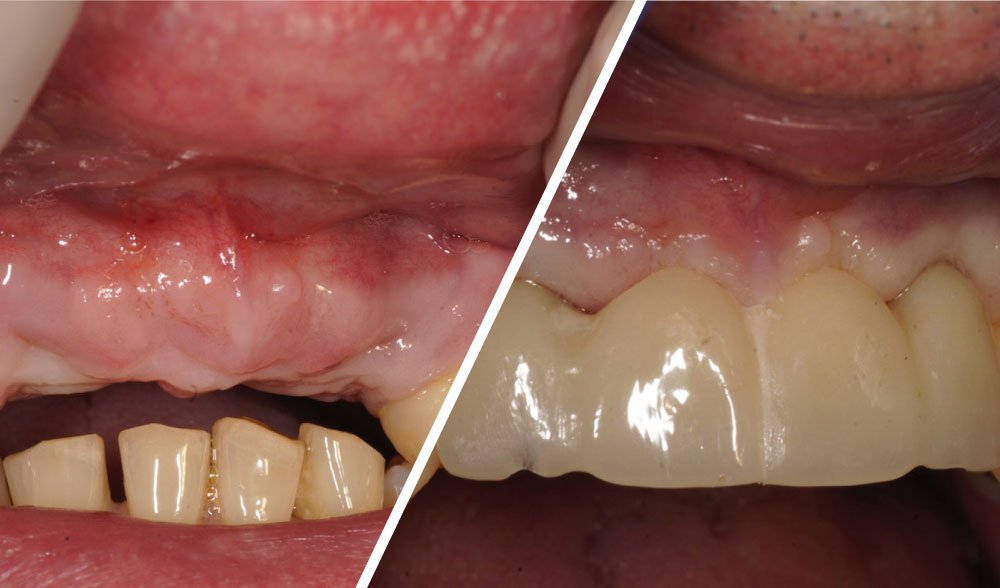

Fractured implants in the mandible

Fractured implants; removal of the implants, ridge reconstruction with Lamina®, MP3® and autogenous bone and placement of 2 new ExFeel implants after 4 months healing period.